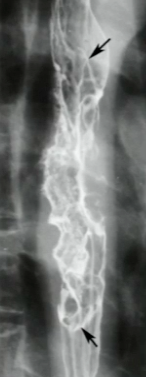

What is your diagnosis in this patient with liver disease?

Uphill varices. Note the serpigineous nodularity in the distal esophagus. This is a result of portal hypertension